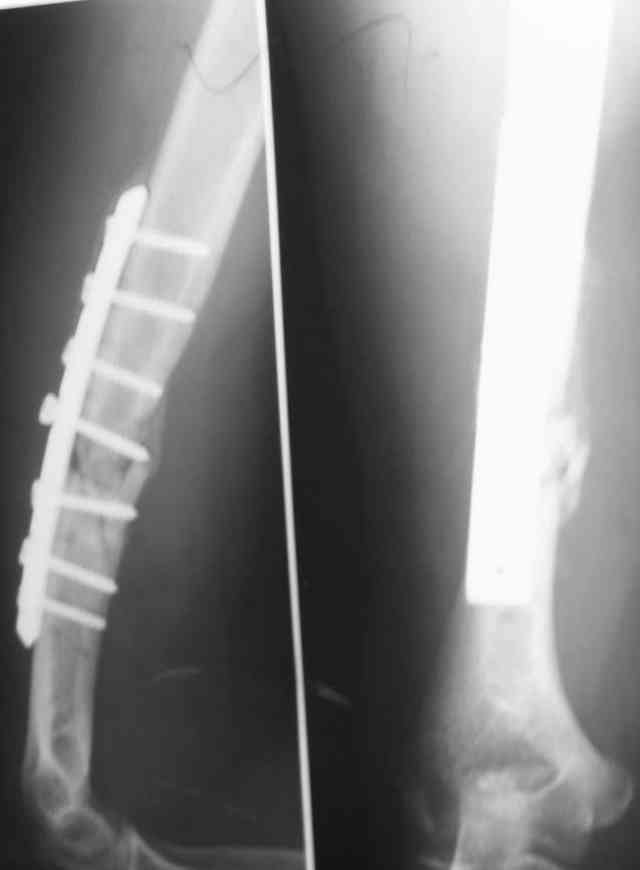

Уважаемые коллеги! Помогите в выборе тактики лечения больной Р.,56 лет, с болтающимся ложным суставом с/3 правой плечевой кости 2-х летней давности. В анамнезе - бронхиальная астма, гормонозависимая форма, ожирение III cт. Травма - автодорожная, получила закрытый многооскольчатый перелом диафиза плечевой кости со смещением (от метафиза до метафиза), в экстренном порядке нами произведен закрытый остеосинтез стержневым аппаратом, отломки удалось сопоставить анатомически. В дальнейшем больная выпала из поля зрения. Как потом выяснилось, после снятия стержневого аппарата, больная долечивалась по Илизарову специалистом из г. Кургана. Аппарат Илизарова удален из-за нагноения мягких тканей. Последние два года работая бухгалтером, фиксирует плечо ортезом. Теперь вновь обратилась к нам для ликвидации ложного сустава.

Штифт - отвисание проксимального отдела - накостный остеосинтез, нагноение, АФВ с ревизиями раны, опять пластина и снова нестабильность. Была удалена пластина и выполнен БИОС штифтом ChM (ДЕОСТ). Через 2 нед. пациент сел за руль и вышел на работу. Причем так и работает до сих пор уже 1,5 года, хотя полного сращения мы вроде бы не достигли ( снимки пришлю позже) - пациент не приходил на осмотры, общался только по телефону.